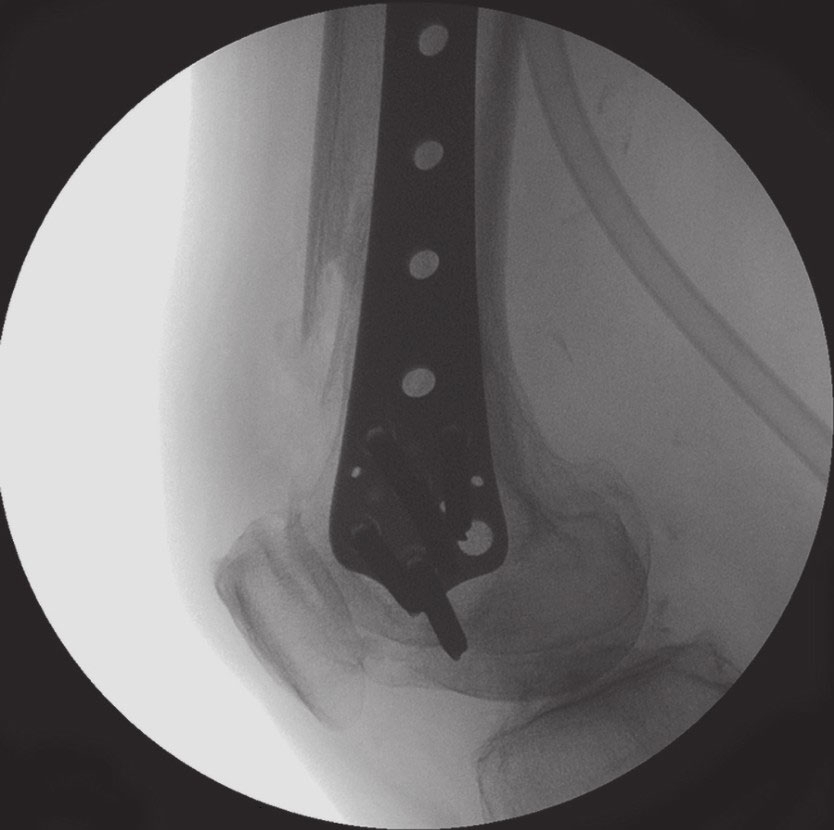

钢板平整放于外侧髁倾斜的平面

远端锁定螺钉放置需与膝关节平行。钢板需平整放置于外侧髁的倾斜表面上。

钢板底面边缘需与股骨后侧皮质平行

钢板位置需在前后位和侧位透视下确认。钢板后缘需与股骨后侧皮质平行。

首先放置远端锁定螺钉。股骨干侧方移位能通过位置螺钉或牵引装置进行调整复位。然后使用多个头部锁定螺钉固定近端部分。依据骨的质量决定是否选择使用双皮质螺钉。

透视确保螺钉和钢板的位置正确

缝合切口前,透视确保螺钉和钢板的位置正确。